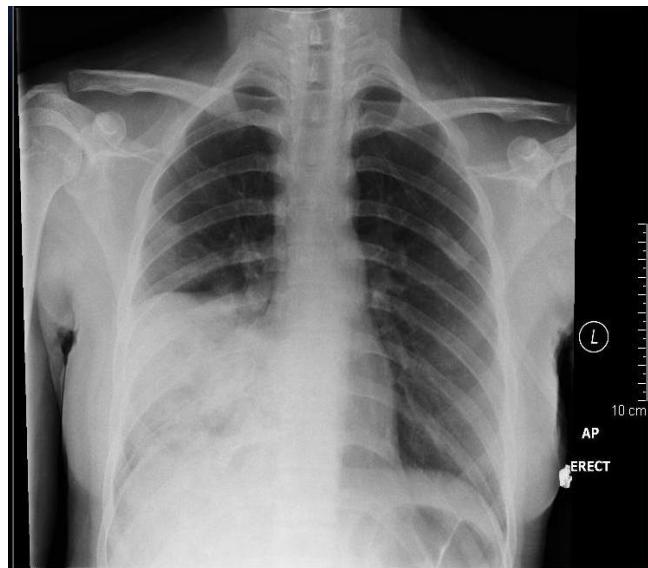

Lung Abscess

- Diagnosis: Lung Abscess.

- Findings:

- Cavitation with an air-fluid level and surrounding consolidation.

- May show a curvy line (associated with unresolved Pneumonia, e.g., Klebsiella).

- Management: IV Antibiotics, potentially drainage (I&D).